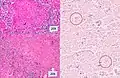

A case of miliary tuberculosis in an 82-year-old woman: